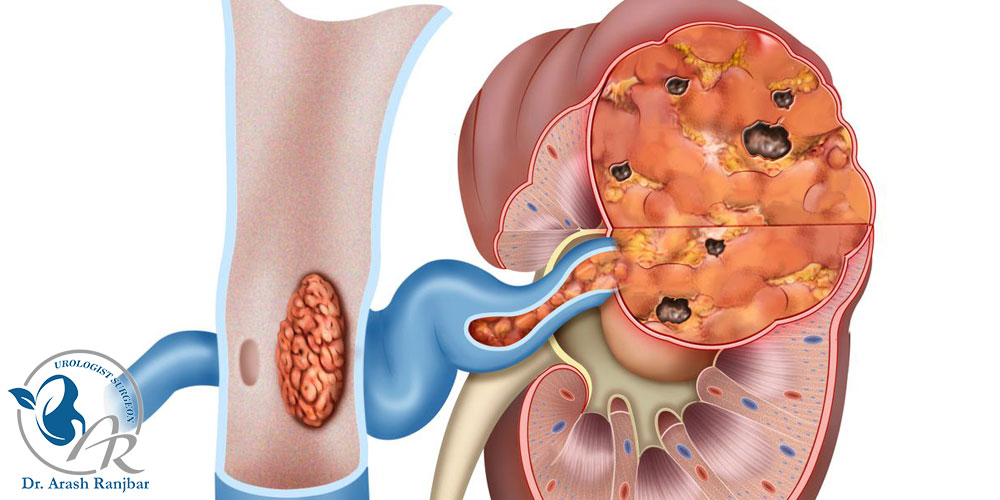

۲. نفرکتومی رادیکال: در این روش، کل کلیه برداشته می شود. گاهی جراح بخشی از حالب، غده فوق کلیوی و حتی غدد لنفاوی نزدیک کلیه را نیز خارج می کند. این عمل زمانی انجام می شود که کلیه به طور کامل درگیر تومور یا بیماری شدید شده باشد.